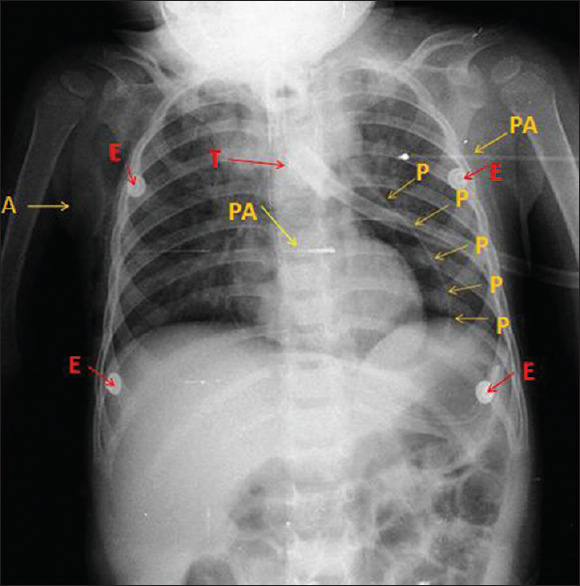

Pneumopericardium: A rare, life-threatening complication of tracheostomy following positive-pressure ventilation to confirm tube position.